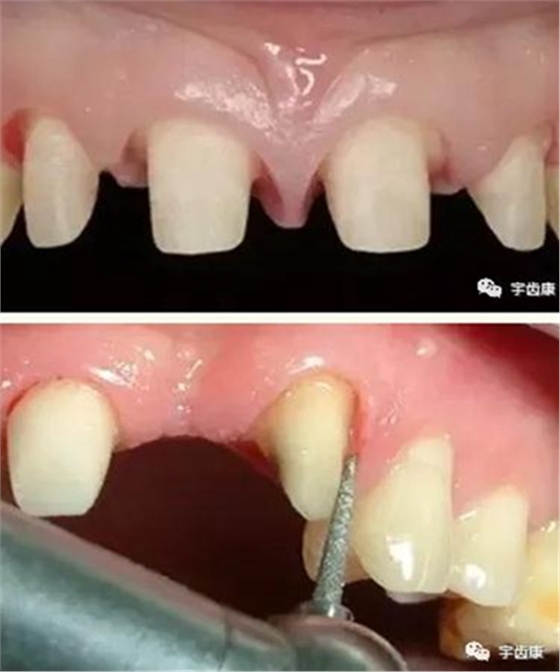

8. 實(shí)際備牙產(chǎn)生的問題

牙體預(yù)備時(shí)需注意的問題

預(yù)備時(shí)注意的問題